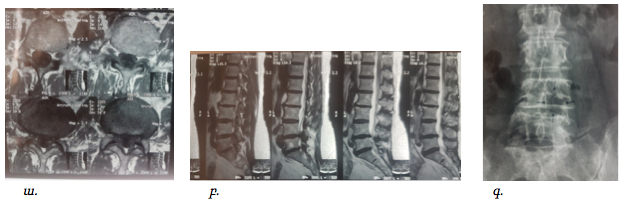

Դուրալ պարկի և նյարդարմատիկի բացազատումից հետո կատարվում էր հսկիչ ռենտգեն հետազոտություն և համեմատվում էր շաղափված ոսկրային պատուհանի չափի և տեղակայման համապատասխանելիությունը նախավիրահատական ՄՌՏ հետազոտությամբ ողնաշարային խողովակի նեղացման հատվածի հետ, ինչի օրինակը պատկերված է նկար 7-ում:

Նկ. 7 Նախա և հետվիրահատական հետազոտությունների համեմատականը

ա. Հիվանդի ՄՌՏ հետազոտում, առկա է ողնաշարային խողովակի արտահայտվածնեղացում L4-L5 մակարդակի (աքսիալ պրոեկցիա)

բ. Նույն հիվանդի ՄՌՏ հետազոտման պատկերը սագիտալ պրոեկցիայում

գ. ներվիրահատականռենտգեն հետազոտում՝ պատկերված է ՄՌՏ հետազոտմամբ ախտորոշված նեղացման տեղակայմանը համապատասխանող ոսկրային դեֆեկտը L4-L5 մակարդակի (ցույց է տրված սլաքով)

Նման վիրահատությունների արդյունավետության մասին է վկայում նկար 10-ում ներկայացված նախավիրահատական և հետվիրահատականհետազոտությունների համեմատականը:

Նկ. 10 Ողնաշարային խողովակի երկու մակարդակի նեղացումով հիվանդի նախավիրահատական և հետվիրահատական հետազոտման նկար

ա. ՄՌՏ հետազոտում համաձայն որի առկա է L4-L5 և L5-S1 մակարդակների նեղացում (ցույց է տրված սլաքով)

բ. Նույն հիվանդի հետվիրահատական ռենտգեն հետազոտում, համաձայն որի առկա են L4-L5 և L5-S1 մակարդակների ողերի աղեղների մասնակի հեռացում, ինչը համապատասխանում էր ախտահարված մակարդակներին (ցույց է տրված սլաքով)